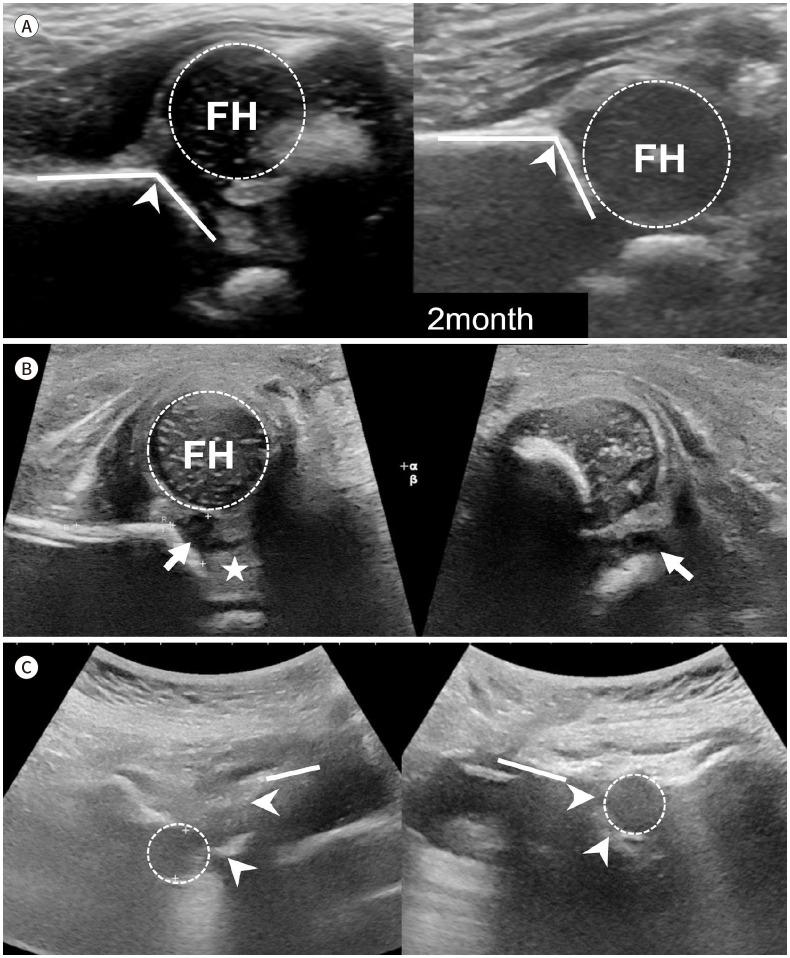

Developmental dysplasia of the hip is a condition characterized by hip joint instability due to acetabular dysplasia in infancy, necessitating precise ultrasound examination. Legg-Calvé-Perthes disease is caused by a temporary disruption in blood flow to the femoral head during childhood, progressing through avascular, fragmentation, re-ossification, and residual stages. Slipped capital femoral epiphysis is a condition where the femoral head shifts medially along the epiphyseal line during adolescence due to stress, such as weight-bearing. Differentiating between transient hip synovitis and septic arthritis may require joint fluid aspiration. Osteomyelitis can be associated with soft tissue edema and osteolysis. When multiple lesions are present, it is essential to distinguish between Langerhans cell histiocytosis and metastatic neuroblastoma. This review will introduce imaging techniques and typical findings for these conditions.

发育性髋关节发育不良是一种因婴儿期髋臼发育不良导致髋关节不稳定的病症,需要进行精确的超声检查。Legg-Calvé-Perthes病是由儿童期股骨头血液供应暂时中断引起的,历经缺血、碎裂、再骨化和残留阶段。股骨头骨骺滑脱是一种在青春期由于负重等压力导致股骨头沿骨骺线向内侧移位的病症。区分暂时性髋关节滑膜炎和化脓性关节炎可能需要进行关节液抽吸。骨髓炎可伴有软组织水肿和骨质溶解。当出现多个病灶时,区分朗格汉斯细胞组织细胞增多症和转移性神经母细胞瘤至关重要。本综述将介绍这些病症的影像学技术和典型表现。